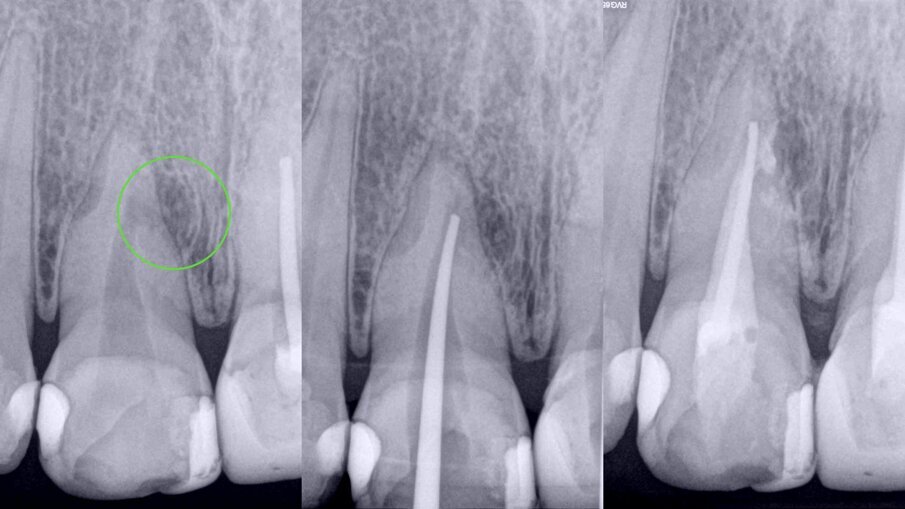

Figs. 6a–c: Radiographic sequence of the treatment performed in tooth #11. Initial radiograph. The root resorption and lateral radiolucent area were evident (a). Working length measurement at the level of the resorption (b). Root resorption repair with a calcium silicate-based material (c).

Figs. 7a–c: Radiographic sequence of the treatment performed in tooth #11. Initial radiograph. The root resorption and lateral radiolucent area were evident (a). Master cone fitting at the level of the complete working length (b). Completed root canal therapy (c).

Fig. 8: Radiographic sequence of the treatment performed in tooth #11. Initial radiograph. The root resorption and lateral radiolucent area were evident (a). Completed root canal therapy (b). Three-year follow-up radiograph showing complete healing of the lateral radicular radiolucent area and the correct sealing of the resorption (c).

During the first appointment for root canal therapy, it was not possible to reach the complete length of the root canal, because the files tended to go inside of the mesial resorption. It was decided to seal the resorptive defect (Fig. 6a–c) using CeraSeal sonically activated using the EQ-S device (Meta Biomed; see video below).

At the second appointment, the material placed at the resorption was completely hard. That hard barrier allowed the file to pass through the entire length of the physiological root canal. The root canal therapy was finished using CeraSeal as the endodontic sealer (Fig. 7a–c). The three-year follow-up radiograph showed complete healing of the lateral radicular radiolucent area (Fig. 8a–c).